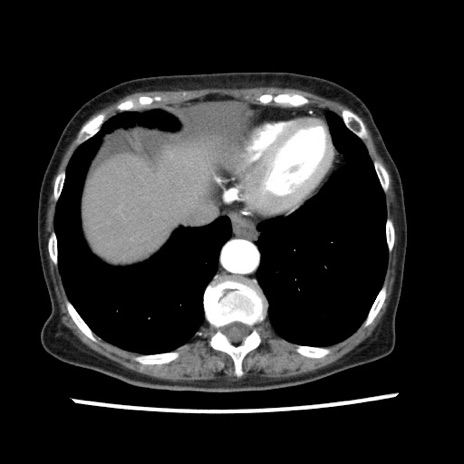

冠状断像

【症例】80歳代女性

【主訴】腹痛

【現病歴】8時間前から腹痛あり来院。

【既往歴】糖尿病、脂質異常症、子宮体癌にて子宮全摘術

【身体所見】意識清明・会話良好だが腹痛で苦悶様、全腹部にわたって反跳痛と圧痛あり

【データ】WBC 13600、CRP 0.14、LDH 224、CK 90